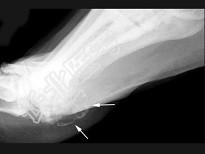

- 单项选择题男,47岁, 关节炎病史20年,结合图像, 最可能的诊断是 ( )

A、类风湿关节炎

B、痛风

C、骨关节结核

D、牛皮癣性关节炎

E、Reiter综合征